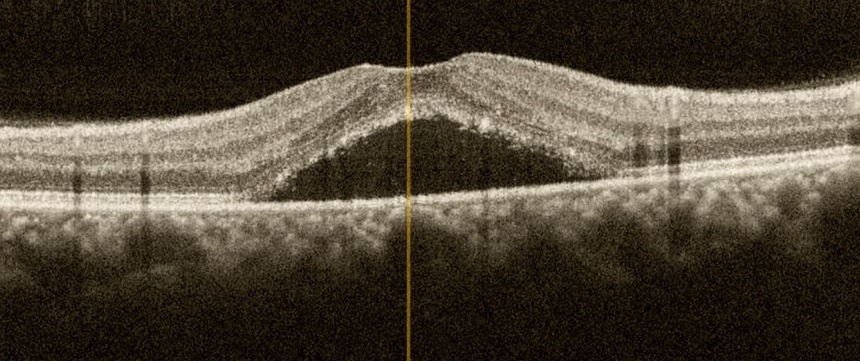

SSR'de OKT görüntüsü

Santral Seröz Retinopati (SSR)

Santral seröz retinopati (SSR) retina altında sıvı birikmesine neden olan bir bozukluktur. Sıvı retinanın dışında yer alan damar tabakadan yani “koroid” dokusundan sızıntı şeklinde yayılarak retinanın altında toplanır ve bu nedenle “santral seröz koryoretinopati” olarak da adlandırılır. Aniden ve ağrısız görme kaybıyla başlayan bu durum erkeklerde daha fazla görülür ve sıklıkla kendiliğinden iyileşir. Ancak tekrar edebilir, hatta bazen kronik hale gelir ve bu durum kalıcı görme kaybıyla sonuçlanabilir.

Tanıda rutin göz muayenesine ilave olarak “optik koherens tomografi” yeterli olmakla birlikte, “flöresein anjiyografi” sızıntının yerinin tespitinde ve olası diğer retina hastalıklarının ayırıcı tanısında yararlıdır.